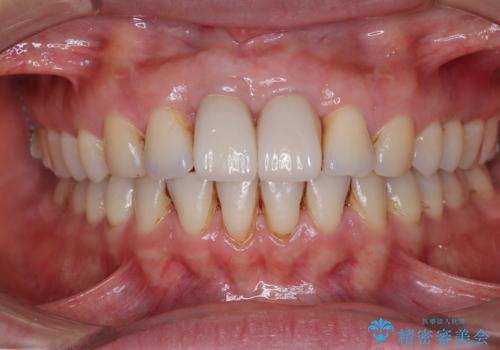

前歯の見た目はもちろん、出血や腫脹のない健全な前歯の状態を獲得することができました。